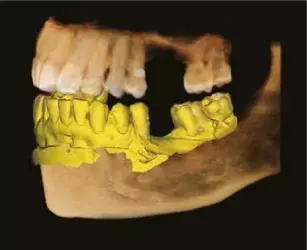

Металлические артефакты часто затрудняют визуализацию и снижают достоверность диагностики. Технология ART-V эффективно подавляет эти артефакты, обеспечивая четкие и детализированные изображения, которые дают вам больше уверенности в результатах диагностики при планировании имплантации и создании хирургических шаблонов.

3D-сканирование моделей: переход в цифровую эпоху:

3D-сканирование моделей позволяет врачам хранить гипсовые слепки в цифровом виде, упрощая управление данными и оптимизируя рабочие процессы.

Интеграция с CAD/CAM-системами: бесшовный цифровой процесс:

Green16 обеспечивает достаточный уровень детализации для создания хирургических шаблонов, обеспечивая бесшовную интеграцию с CAD/CAM-системами.

• Автоматическая сегментация зубов и костей с возможностью экспорта данных в формате STL.